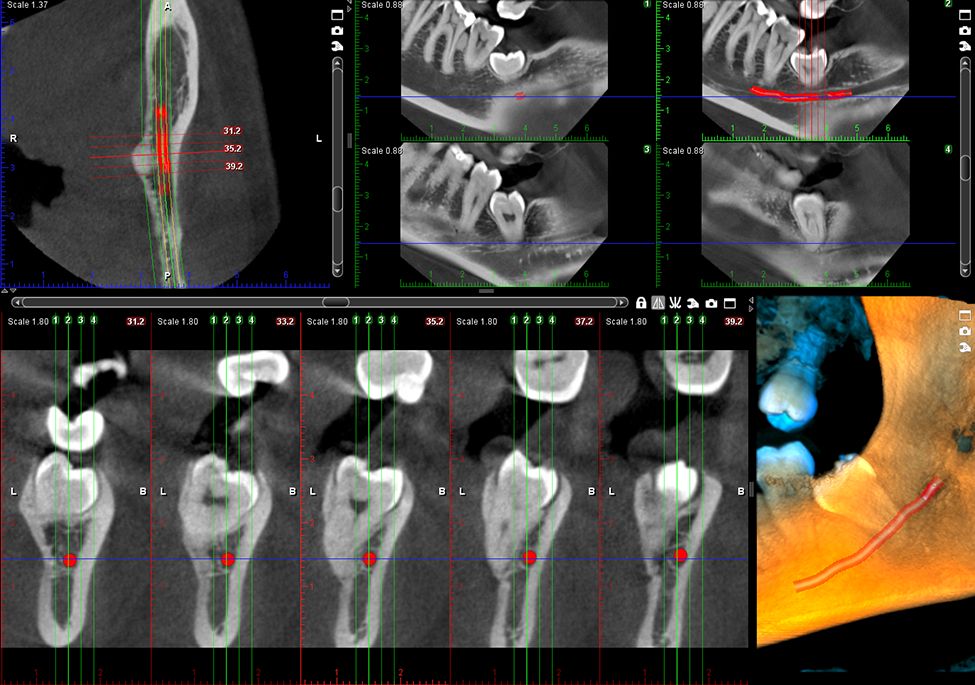

Wysokiej jakości obrazowanie endodontyczne

Dzięki wielkości woksela 75 μm, nasz tryb obrazowania endodontycznego jest idealny do wykonywania zdjęć małych szczegółów anatomicznych. Wyjątkowo wysoka rozdzielczość pozwala wyraźnie widzieć nawet najbardziej wymagające obszary zabiegowe.

Obrazy Kliniczne Planmeca ProMax 3D Plus